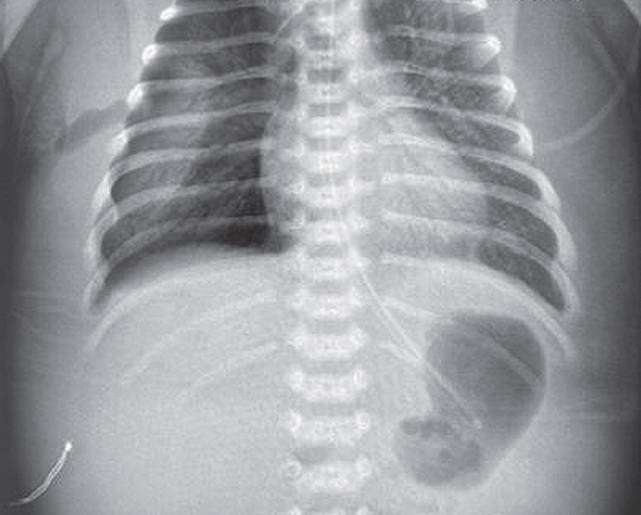

В статье представлен случай успешного лечения острого респираторного дистресс-синдрома у доношенного новорожденного, осложнившегося баротравмой легких, с применением монобронхиального введения экзогенного сурфактанта под рентгенологическим контролем. С целью оценки течения заболевания и эффективности лечения проведен ретроспективный анализ медицинской документации. С первых минут жизни у ребенка отмечались дыхательные расстройства, что стало основанием для проведения неинвазивной искусственной вентиляции легких. В динамике выявлено прогрессирование гиперкапнии и гипоксемии, в связи с чем была выполнена интубация трахеи и начата конвекциональная искусственная вентиляция легких с FiO2 = 1,0. Ключевой элемент терапии, позволивший достичь стабилизации состояния и регрессирования нарушений газообмена с полным выздоровлением пациента, — монобронхиальное введение экзогенного сурфактанта.